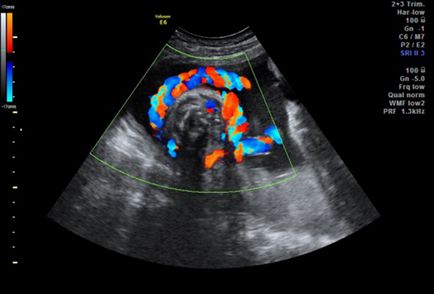

fat folosind studiu de ultrasunete cu RDC

Ultrasunete a fatului cu RDC încolăcit în jurul cordonul ombilical

Fructul este recomandat să examineze în cazul în care mama și copilul diferiți factori Rhesus (la femei este negativ, și pozitiv al copilului). Este nevoie de cercetare, în cazul în care fătul este în uter lateral sau oblic, precum și la stabilirea că dezvoltarea mai multor copii. ecografie specială este necesară, desigur, și atunci când copilul ovivaetsya cablul de gât. În cazul în care fătul suferă de o boală cromozomială, în curs de dezvoltare preeclampsie sau polyhydramnios.

Doppler color fetale